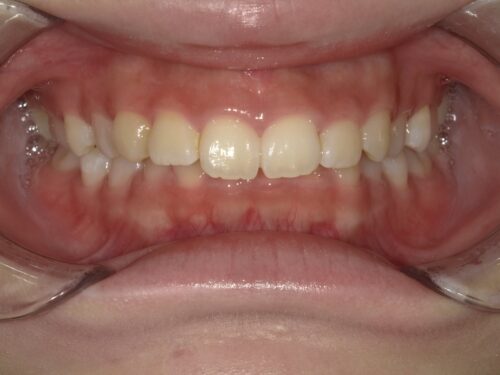

治療後・正面の写真

パッと見た時の印象が違いますよね。前歯の出っ張りが改善され、歯並びがきれいに整っています。